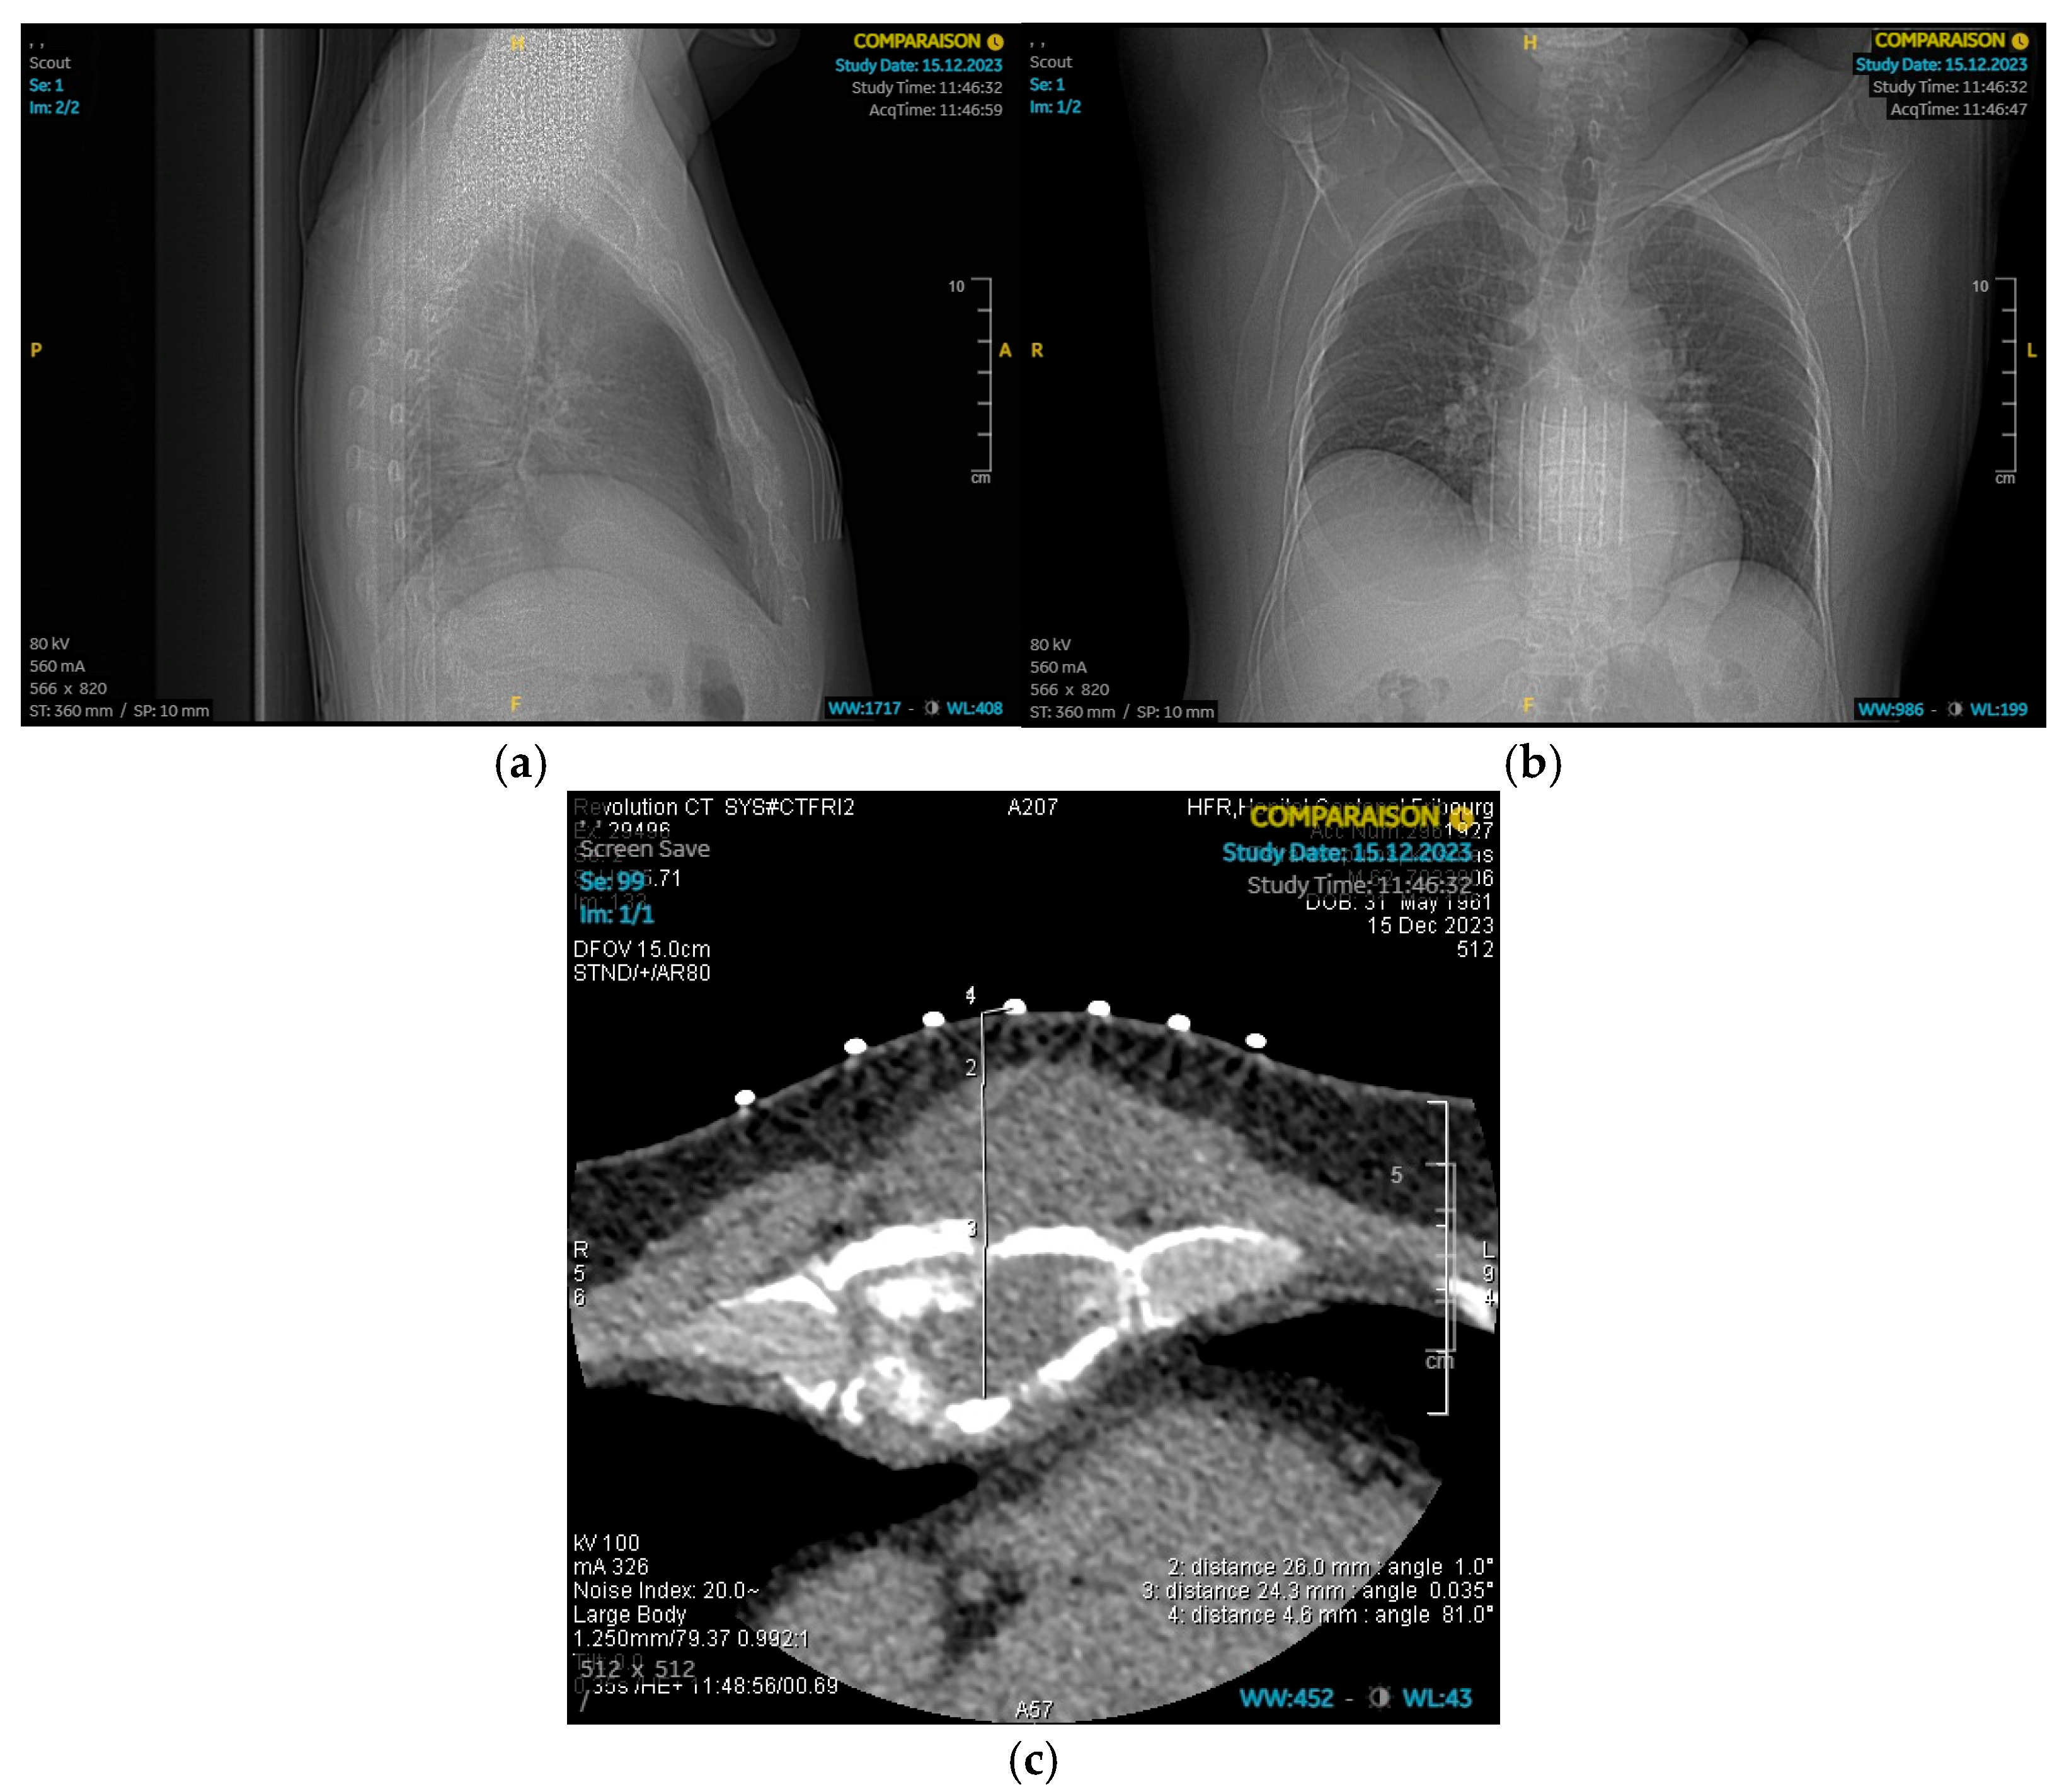

2. Case Presentation

2.1. Patient Background

2.2. Surgical Procedure